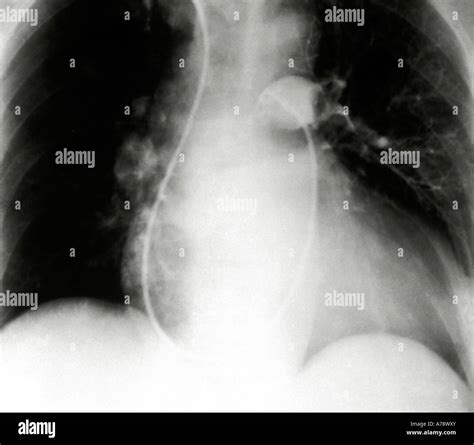

An X-ray is a common imaging technique used to visualize the internal structures of the body. In the context of a lung embolism, a Lung Embolism X Ray can provide valuable information about the condition of the lungs and the presence of any blockages. However, it is important to note that while an X-ray can help rule out other conditions, it is not always sufficient to confirm a lung embolism on its own.

When a lung embolism is suspected, a Lung Embolism X Ray may reveal:

• Enlarged pulmonary arteries

• Pleural effusion (fluid around the lungs)

• Atelectasis (collapse of lung tissue)

• Pneumonia or other lung infections

However, these findings are not specific to a lung embolism and can be seen in other conditions as well. Therefore, additional diagnostic tests, such as a CT scan or a ventilation/perfusion (V/Q) scan, are often required to confirm the diagnosis.